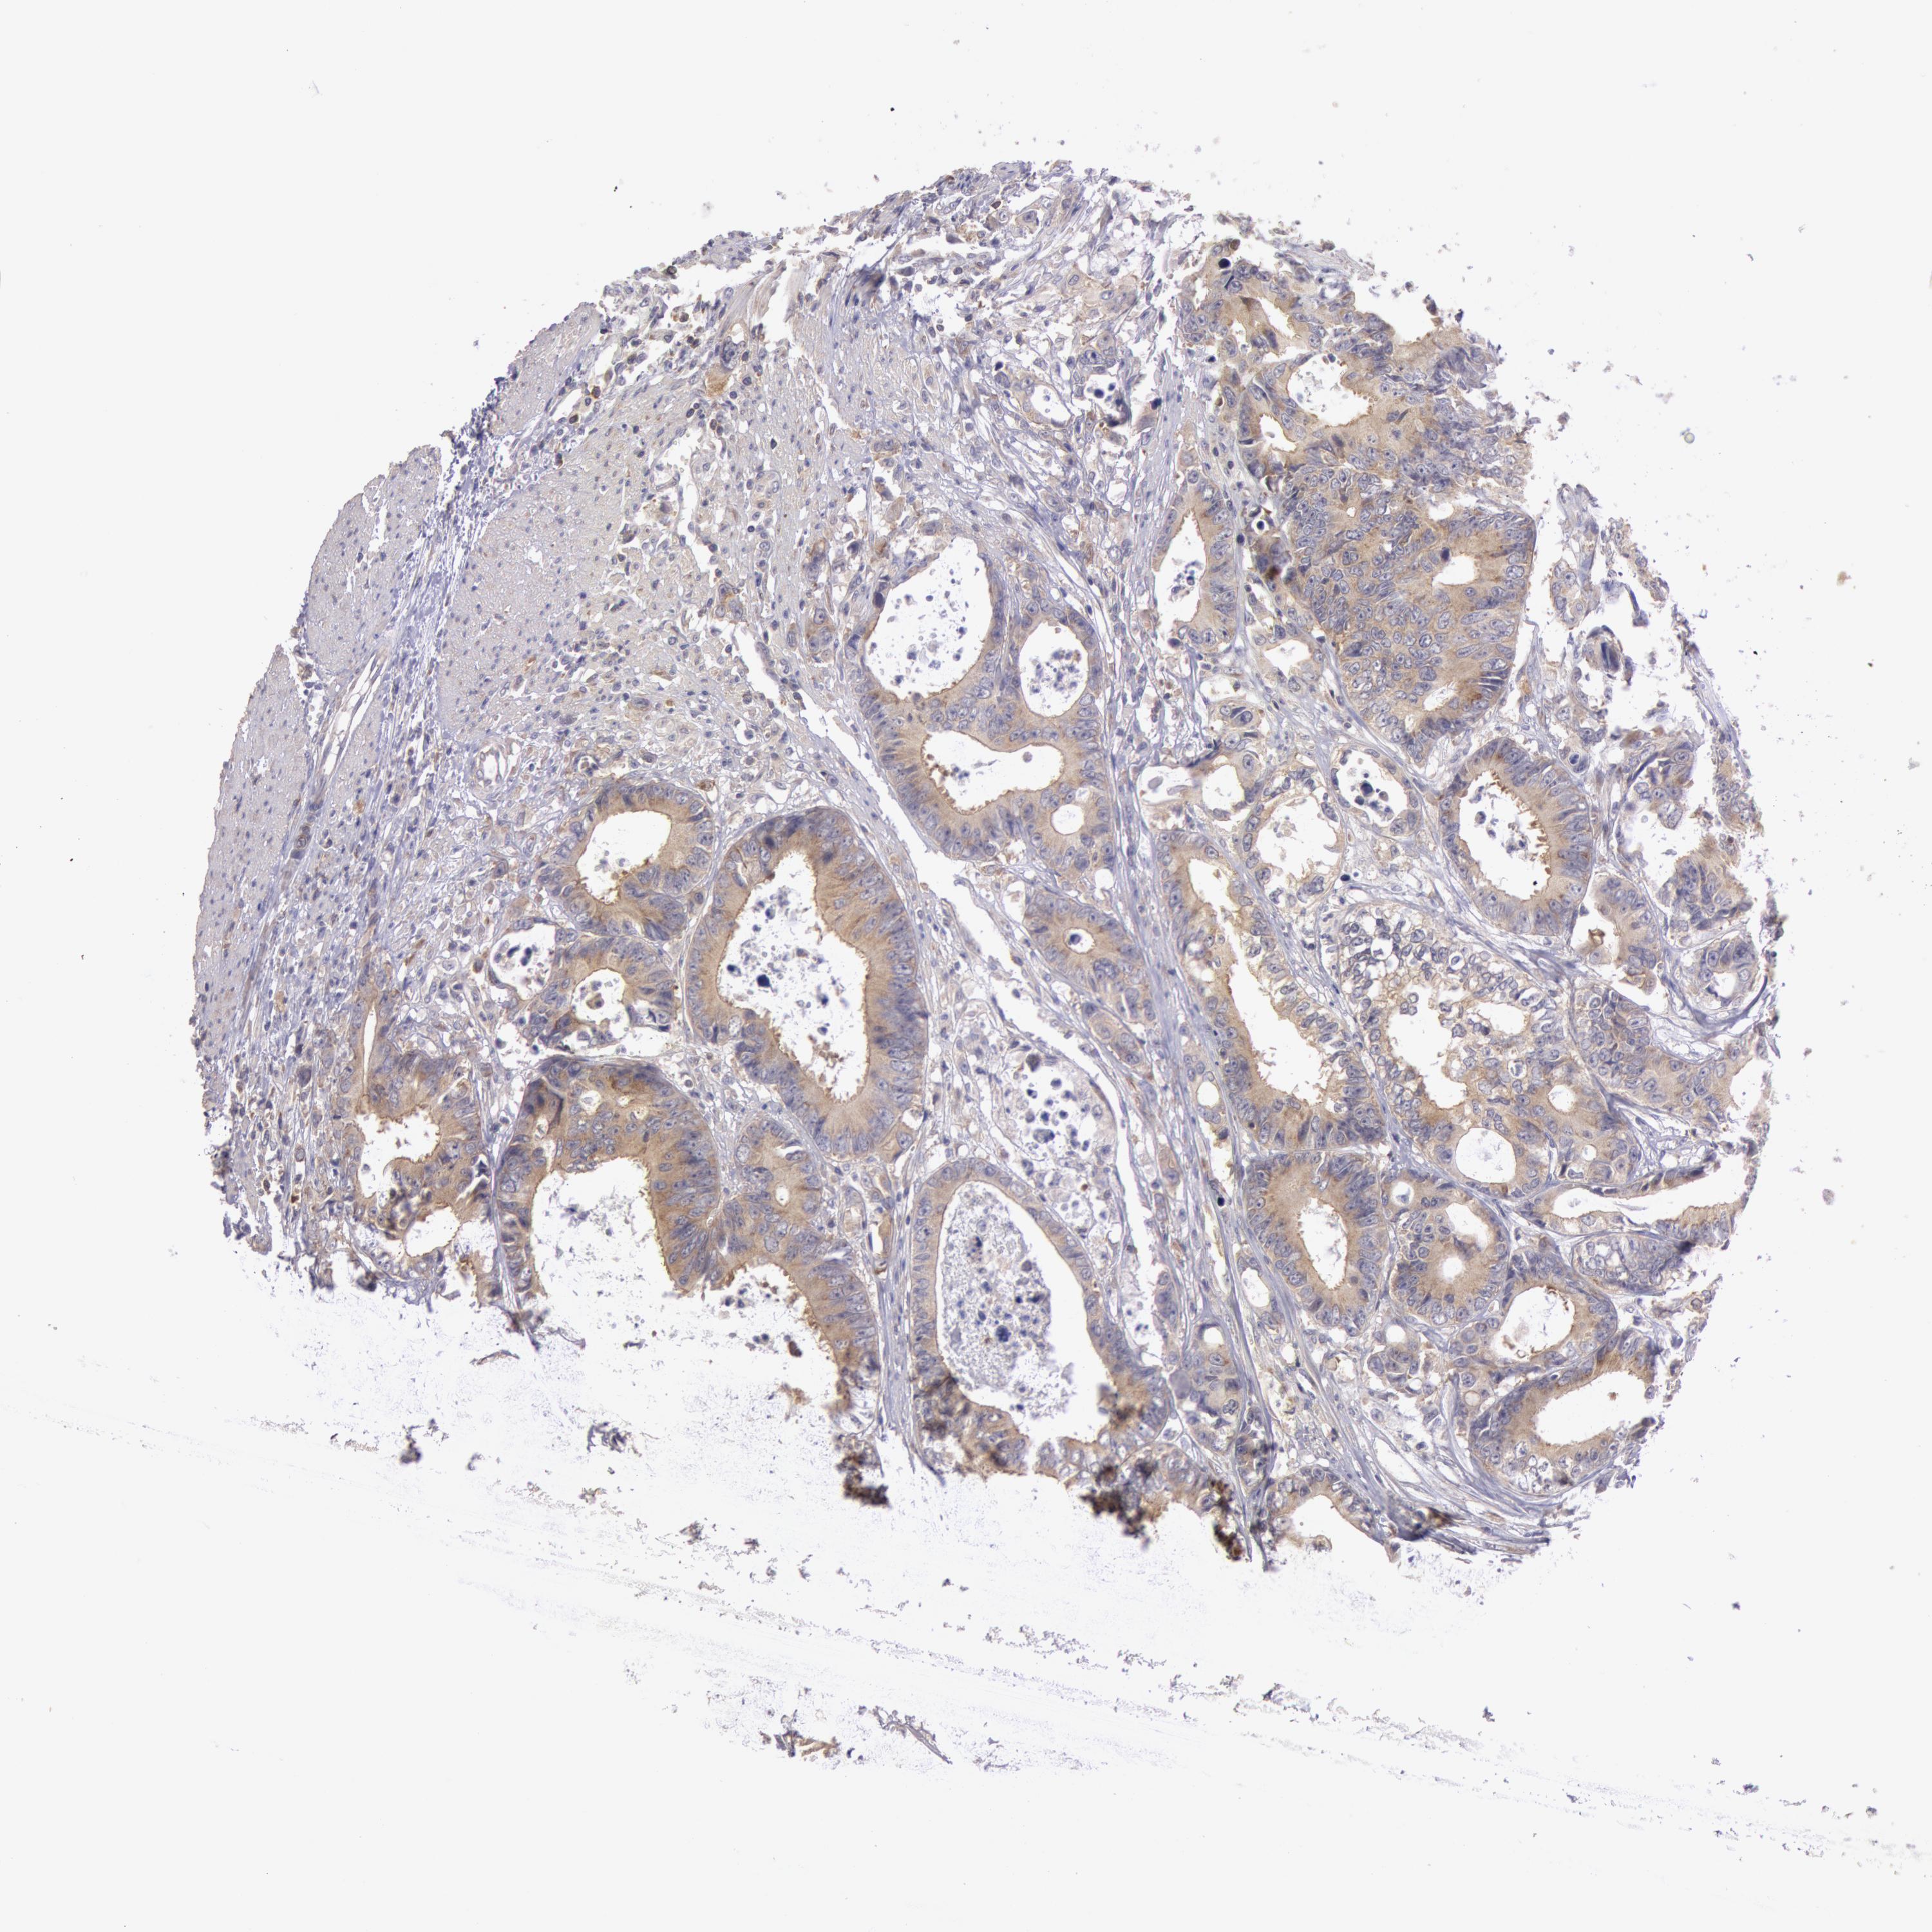

CANCER COLORECTAL CANCER Show tissue menu

Colorectal cancer

Human cancer

Colon adenocarcinoma